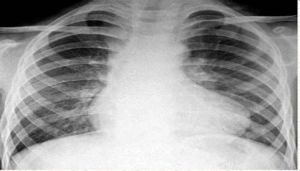

主動脈結就是主動脈弓由轉向左處突出於胸骨左緣的地方。主動脈結就是主動脈弓由右轉向左處突出於胸骨左緣的地方,它平對左胸第二肋軟骨。肺動脈段位於主動脈結下方,對判斷主動脈粥樣硬化很有意義。先心病時,主動脈結常縮小。

主動脈結就是主動脈弓由右轉向左處突出於胸骨左緣的地方,它平對左胸第二肋軟骨。肺動脈段位於主動脈結下方,對判斷主動脈粥樣硬化很有意義。